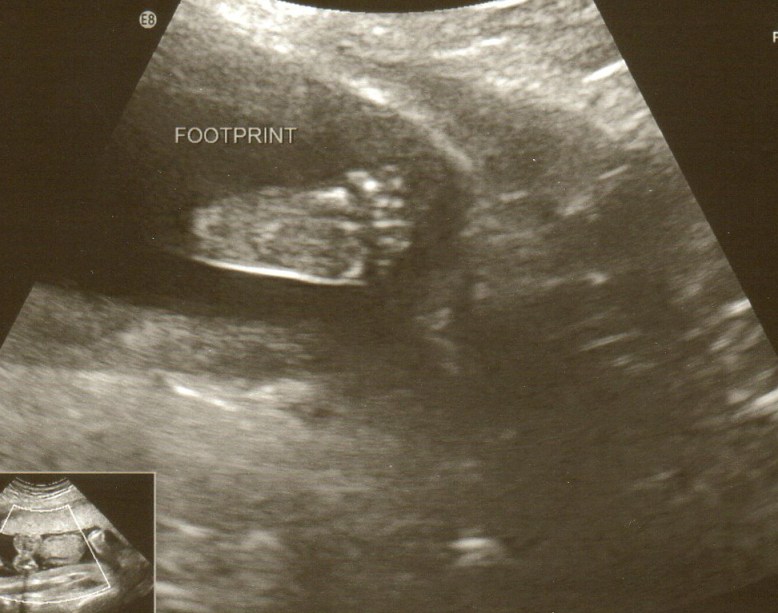

With this cute little thing!

I know, I know… it’s a foot. But it’s attached to a cute little thing, I promise! And a cute little GIRL thing at that! 🙂